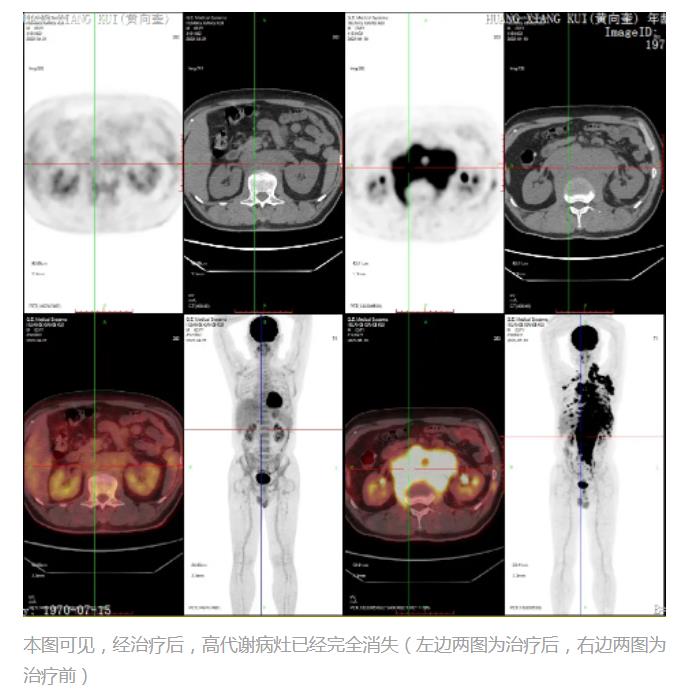

战胜血液系统癌症的新“武器”CAR-T细胞疗法